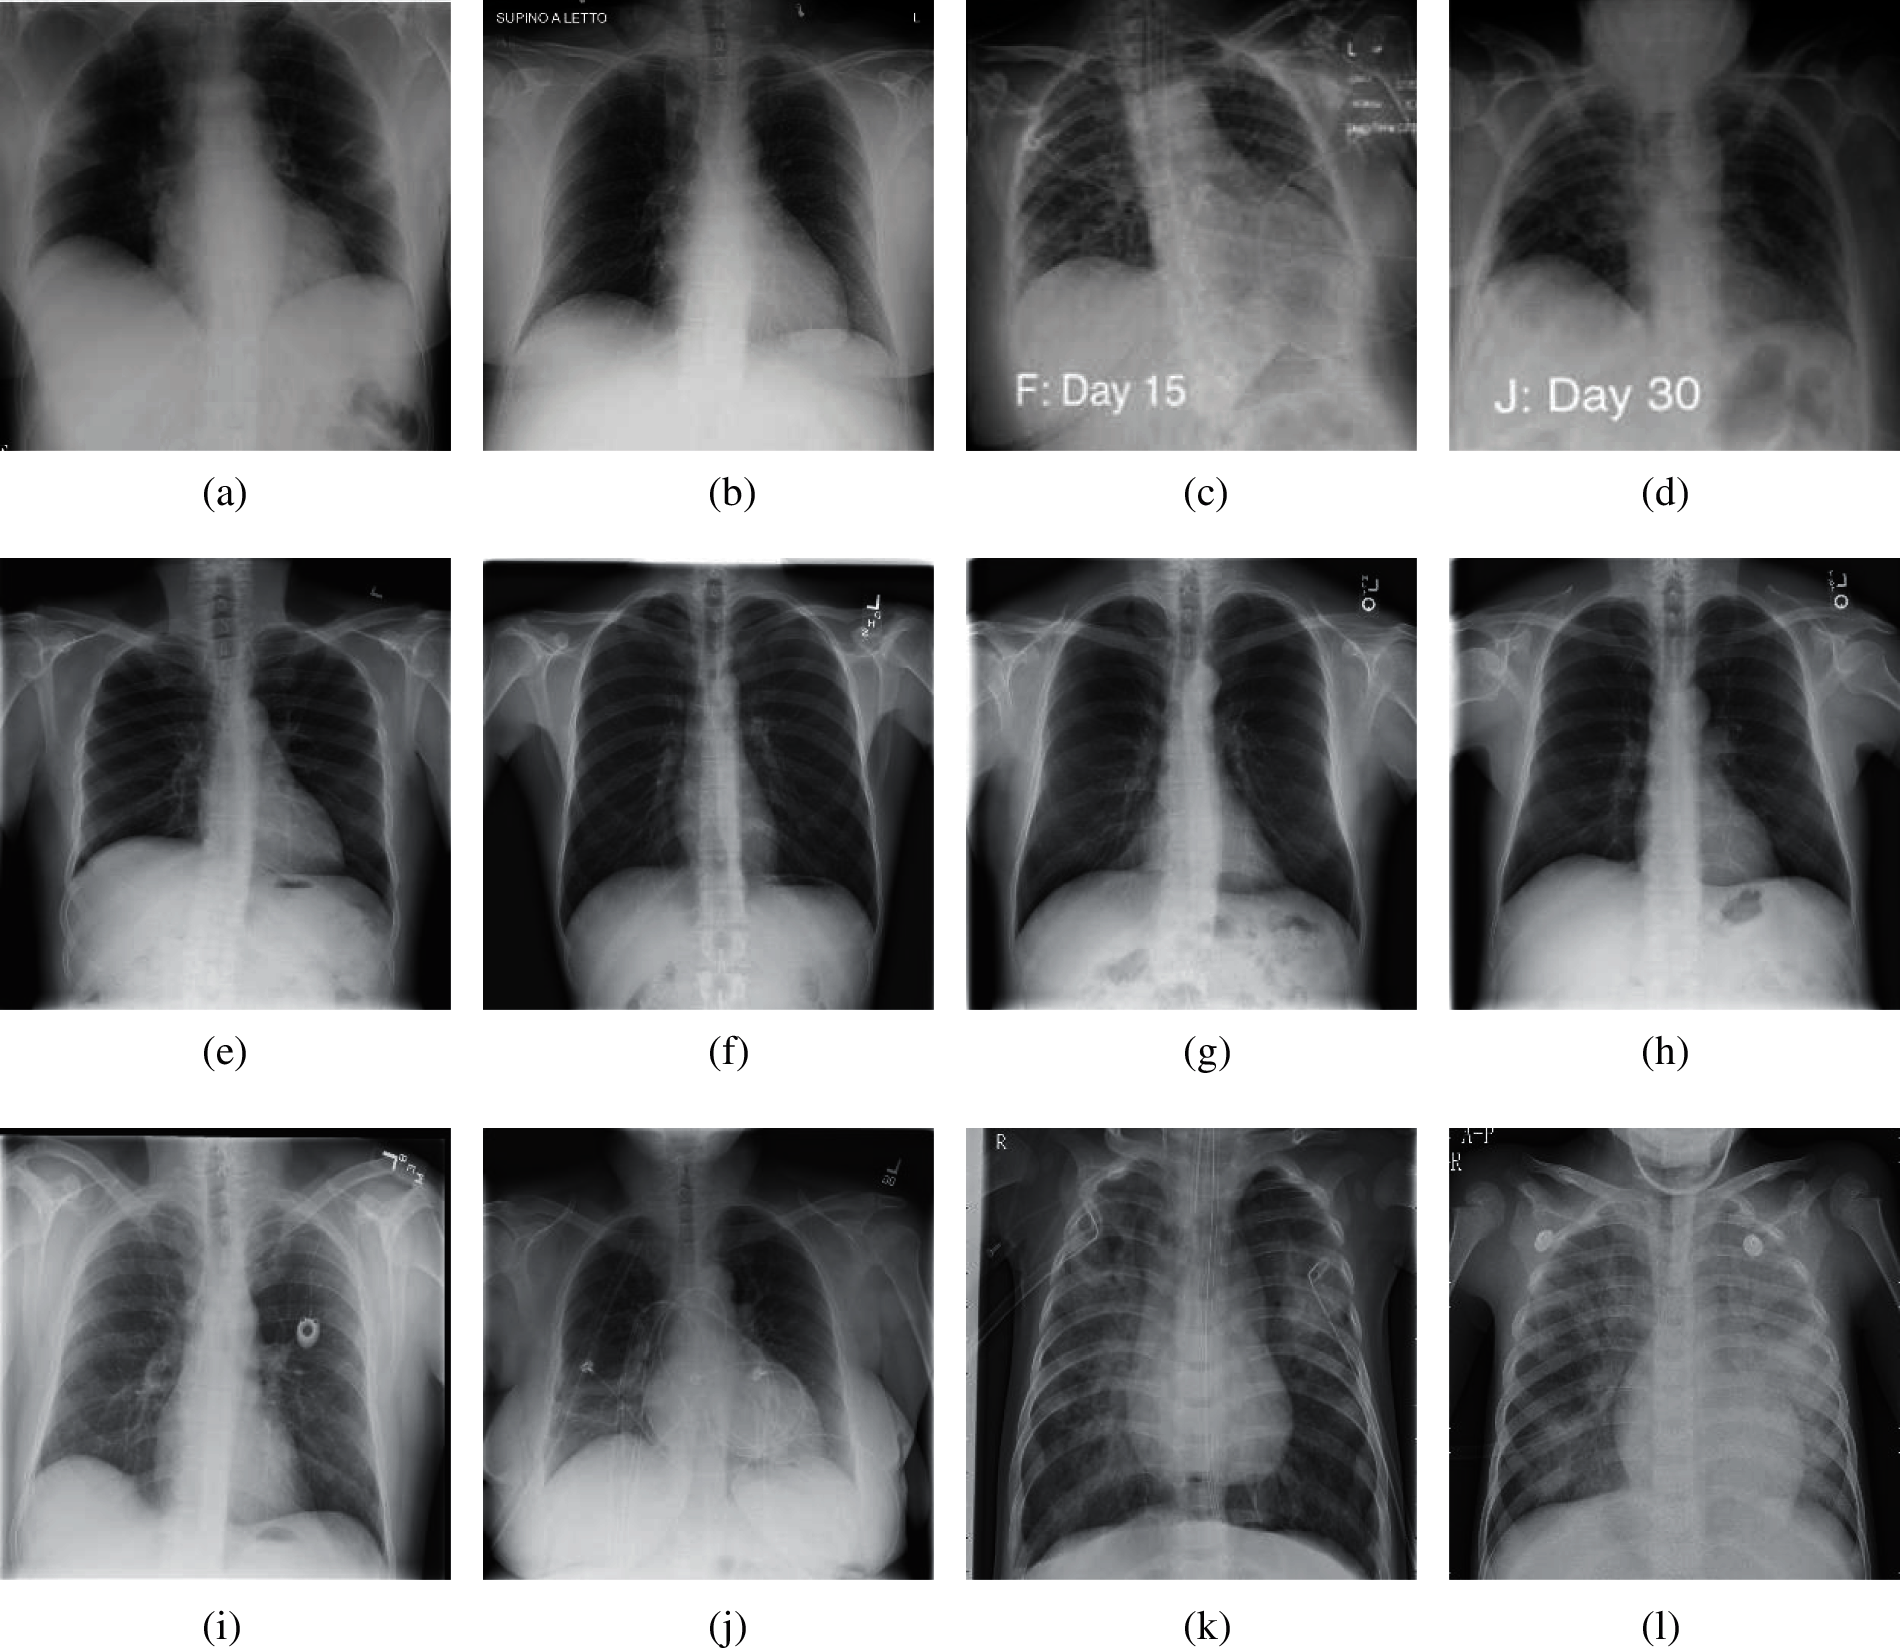

The experimental dataset used in this paper is a public dataset from the Kaggle website [13]. This dataset consists of 6939 chest X-ray images, which are divided into three categories (COVID-19, Normal, and Pneumonia), and each category has 2313 images. The number ratio of each category of chest X-ray images is 1:1:1. In each category image, 80% of the samples were randomly selected as training set and 20% of the rest were used as test set. In Section 4, we keep the same division ratio of training set and test set to perform 10-fold cross validation. The experimental results are from NVIDIA QUADRO RTX 8000. The other parameters of the device are as follows. GPU memory is 48 GB GDDR6 with ECC. Total graphics power is 260 W. NVIDIA tensor cores is 576. NVIDIA RT cores is 72. And the total board power is 295 W. Fig. 2 shows the chest X-ray images from our dataset.

Figure 2: Samples of our dataset (a) Sample 1 of COVID-19 (b) Sample 2 of COVID-19 (c) Sample 3 of COVID-19 (d) Sample 4 of COVID-19 (e) Sample 1 of normal (f) Sample 2 of normal (g) Sample 3 of normal (h) Sample 4 of normal (i) Sample 1 of pneumonia (j) Sample 2 of pneumonia (k) Sample 3 of pneumonia (l) Sample 4 of pneumonia

According to Fig. 2, we can see that for the chest of X-ray images of COVID-19, it is usually manifested as multiple ground glass shadows and infiltrating shadows in both lungs. If the condition is serious, pulmonary consolidation can occur, but pleural effusion is rare. For the chest X-ray images of pneumonia, there are fuzzy cloud like or uniform infiltration shadow. The hilar is dense, gradually shallow outward, and the edge is not clear. It usually does not invade the whole lung lobe, most of them involve in one lung lobe, especially in the lower lobe.